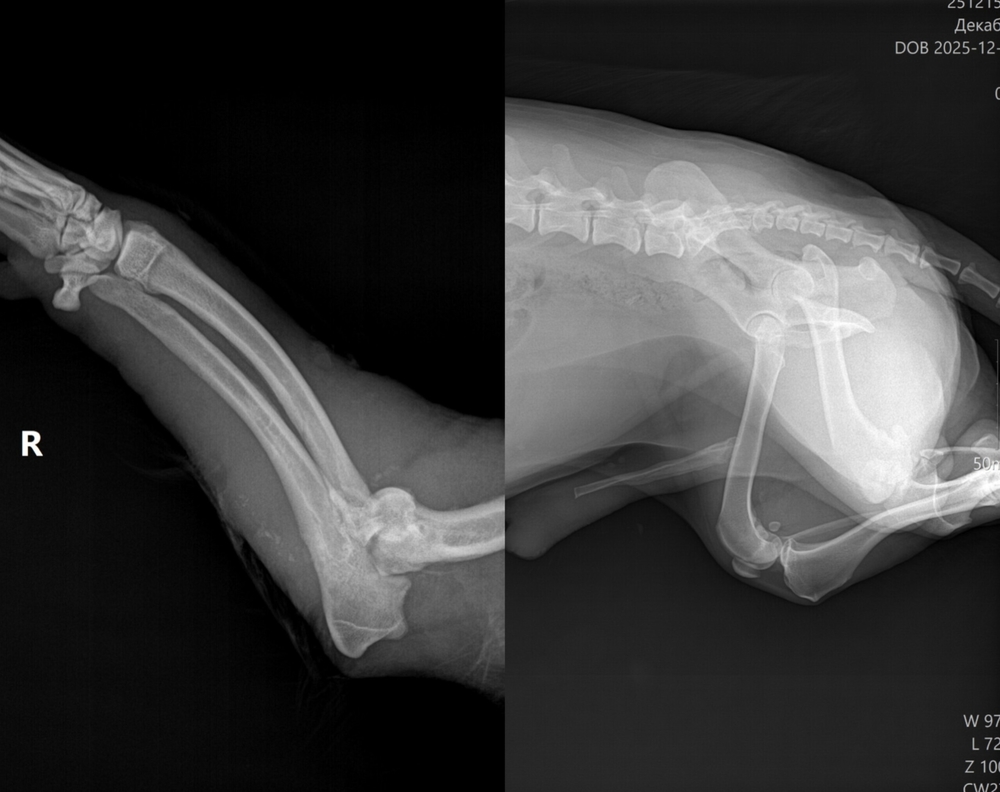

Информируем вас, что на карту администратора Приюта поступили пожертвования в сумме 19 400 руб., и еще 7000 пришли по QR-коду на расчетный счет. Огромное спасибо - вы подарили бедняге шанс на выздоровление! ????У собаки - перелом лапы и множество других неприятных диагнозов. Но лечение идет, раны обработаны, дренажи поставлены и надежда на хороший исход есть. И все это - благодаря вашей помощи.Пожалуйста, держите за песика кулачки - ему всего около пяти лет, и, если повезет, он поправится и еще отыщет себе дом, где будет счастлив.